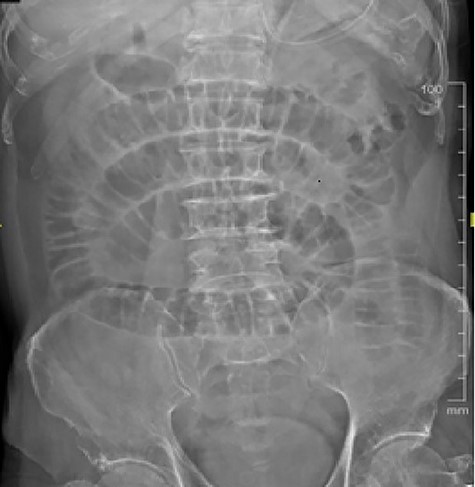

After 5 days, a 61-year-old Indian gentleman presented with generalized abdominal pain and vomiting for 5 days. On examination, his abdomen was distended, but soft and non-tender. CT abdomen revealed dilated small bowel with a suspicious mass at the ileum (Fig. 4). He denied neither swallowing any foreign body nor mushroom. Nasogastric decompression was done, but his condition did not improve with conservative measures. He underwent exploratory laparotomy where an intraluminal mass was found 160 cm from the terminal ileum with collapsed bowel distally. An enterotomy was done and an uncut mushroom was found (Fig. 5). Later on, he recalled that he had indeed consumed a piece of Chinese mushroom 7 days prior to admission.

CT scan showing a suspicious mass at the distal ileum of the second patient.